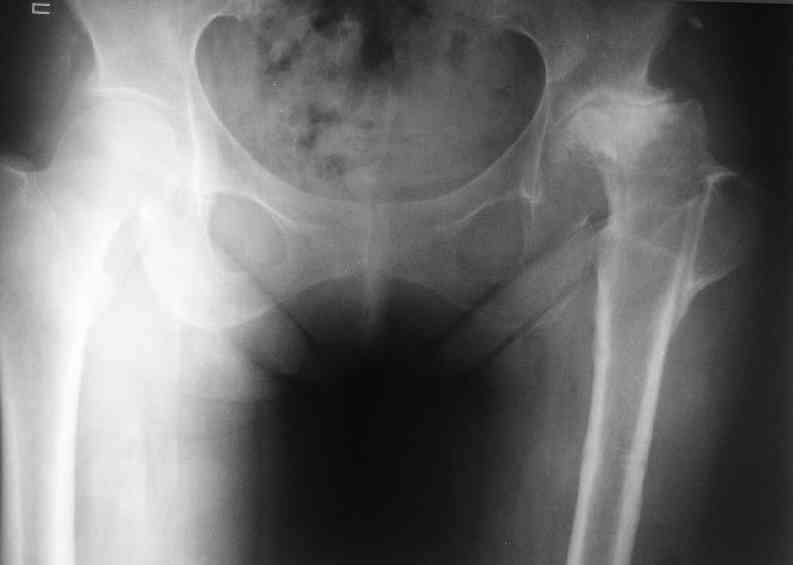

Re: несросшаяся шейка бедра

Не такое уж страшное укорочение по снимкам.Вчера прооперирован похожий случай.Обошлись без релиза и аппаратного низведения. укорочение было 4 сантиметра.Теперь ножки ровные.